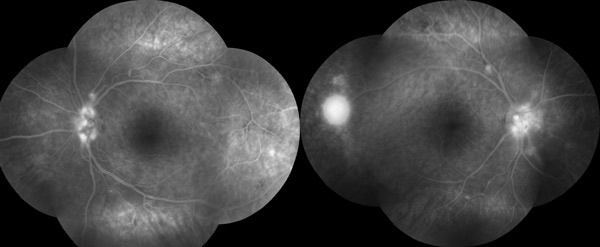

Fluorescein angiogram revealed evidence of inflammation along the arterial walls as well as a marked disc leak. There is arterial aneruysm formation close to or at the arterial bifurcations. Later, scattered retinal non-perfusion led to neovascularisation in the retina in both eyes.